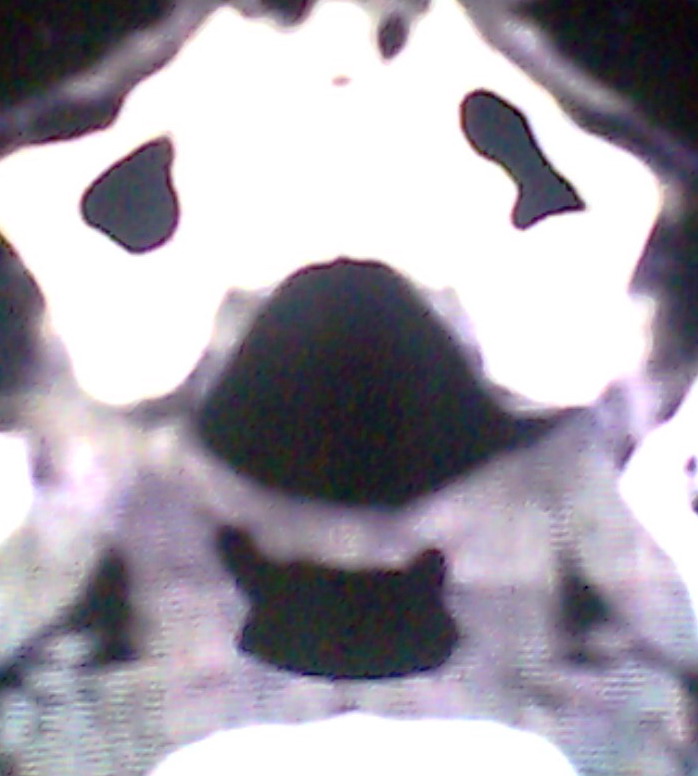

女、18岁,身高1.5左右,鼻塞、流涕数月,两侧瞳孔明显增大,曾与几年前去北京看眼,未发现病变。

考虑起源与蝶窦的粘液囊肿。

支持:考虑起源与蝶窦的粘液囊肿,应该加冠状面扫描

考虑脑膜脑脊液鼻内膨出

考虑起源于蝶窦的粘液囊肿突入鼻咽部。

\"几年前去北京看眼\"不知这句话有何玄机,支持考虑脑膜脑脊液鼻内膨出,膨出口在蝶鞍处

建议冠状面扫描,支持:脑膜鼻内膨出; 蝶窦粘液囊肿突入鼻腔可能性小。

在上级医院冠状位ct扫描后,诊断为:脑膜膨出,已住院准备手术。等待术后结果。